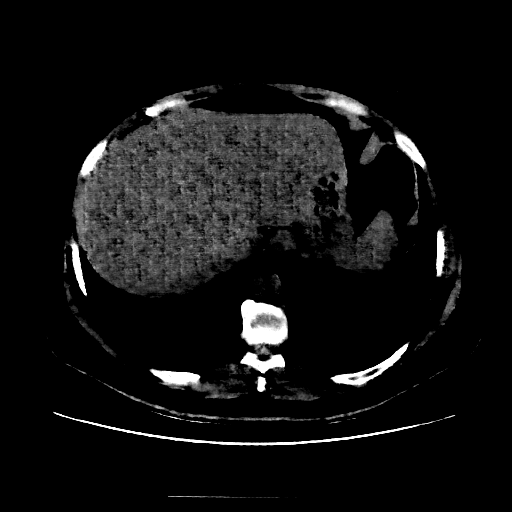

Original NATIVE CT scan (input)

Full window (WL 1023.5, WW 4095 β†’ Low βˆ’1024, High +3071)

Actual HU range: [-160.0, 240.0]